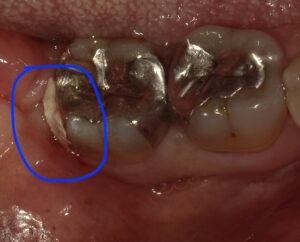

術前の状態です。仮のセメントが詰めてあります。